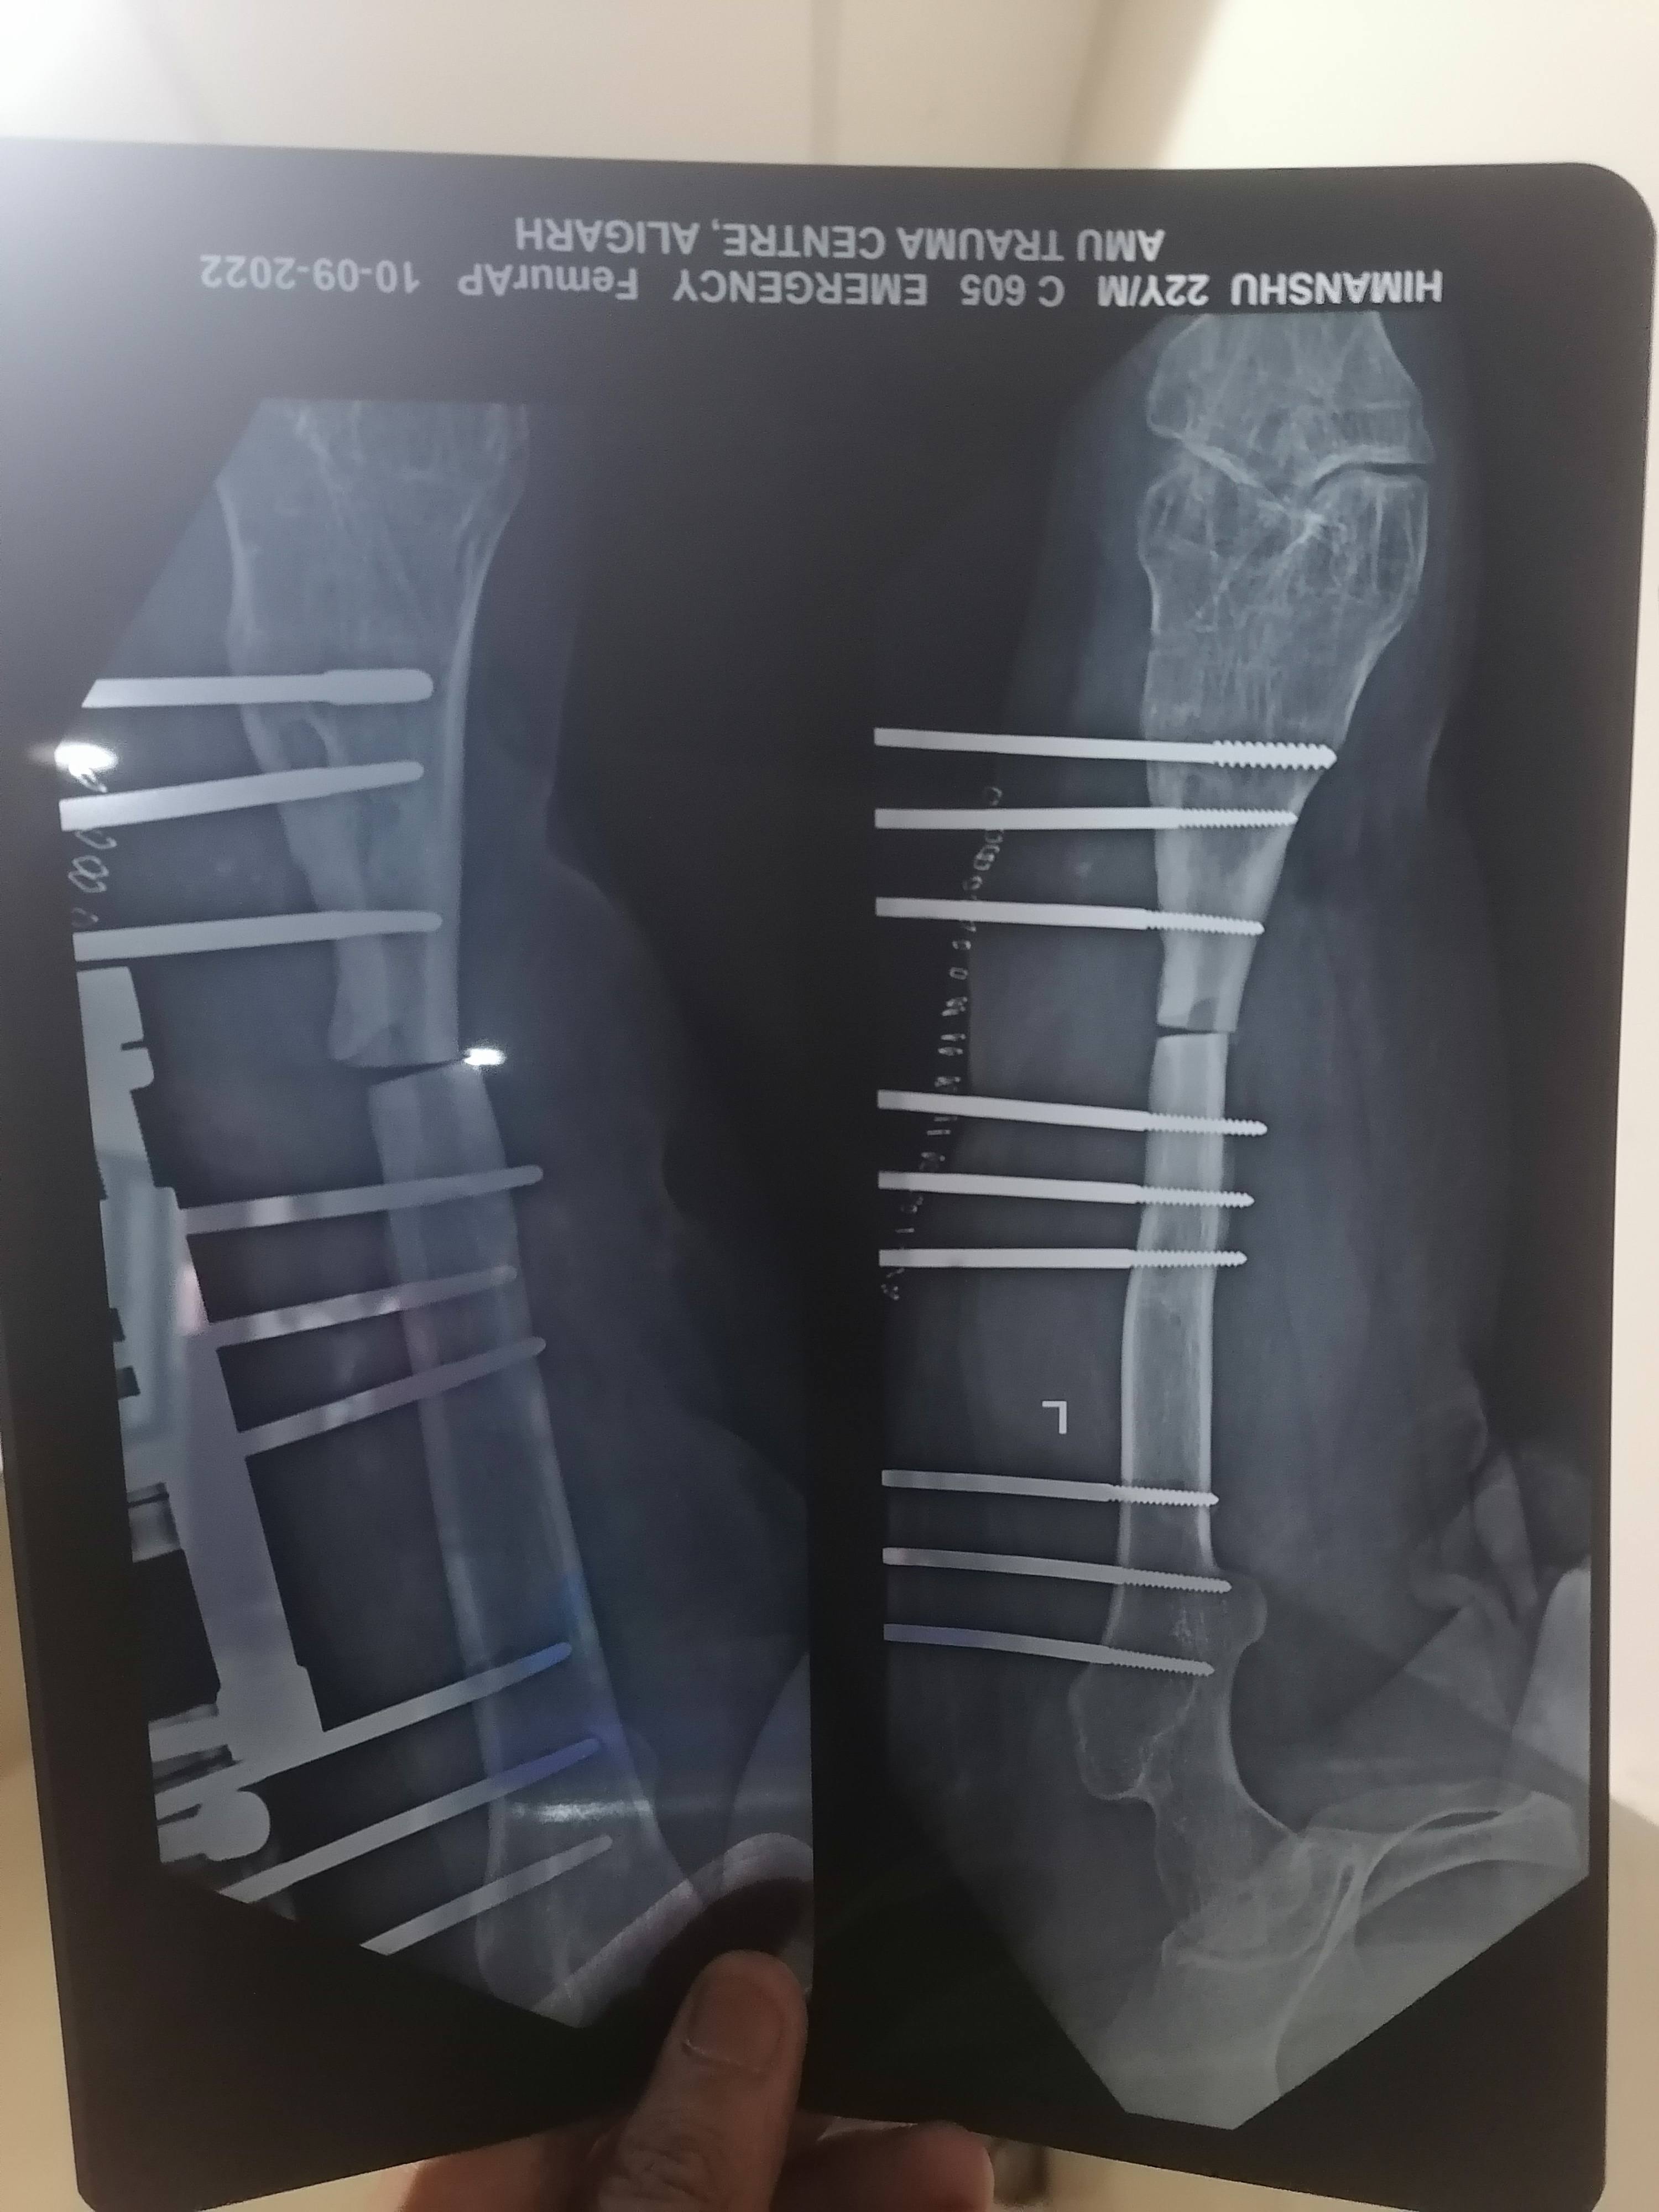

हिमांशु शर्मा

सर मेरे पैर में चोट लगने के कारण 7 साल से हड्डी में पस पड़ गया था फिर सर हड्डी टूट गई और उसमें अब ऑपरेशन कर के गली हुई हड्डी काट के LRS  लगा दिया 3 महीने हो गये पर सर पस बन्द नही है और हड्डी भी गली हुई नही है अब और सर हड्डी जुड़ी नही है और अब 7हप्ते पहले भी सफाई कर दी फिर भी पस आ रहा हैं थोड़ा

Proximal tibai healing huwa hai ya nhi

Proximal tibai fracture healing hai ya nhi sir